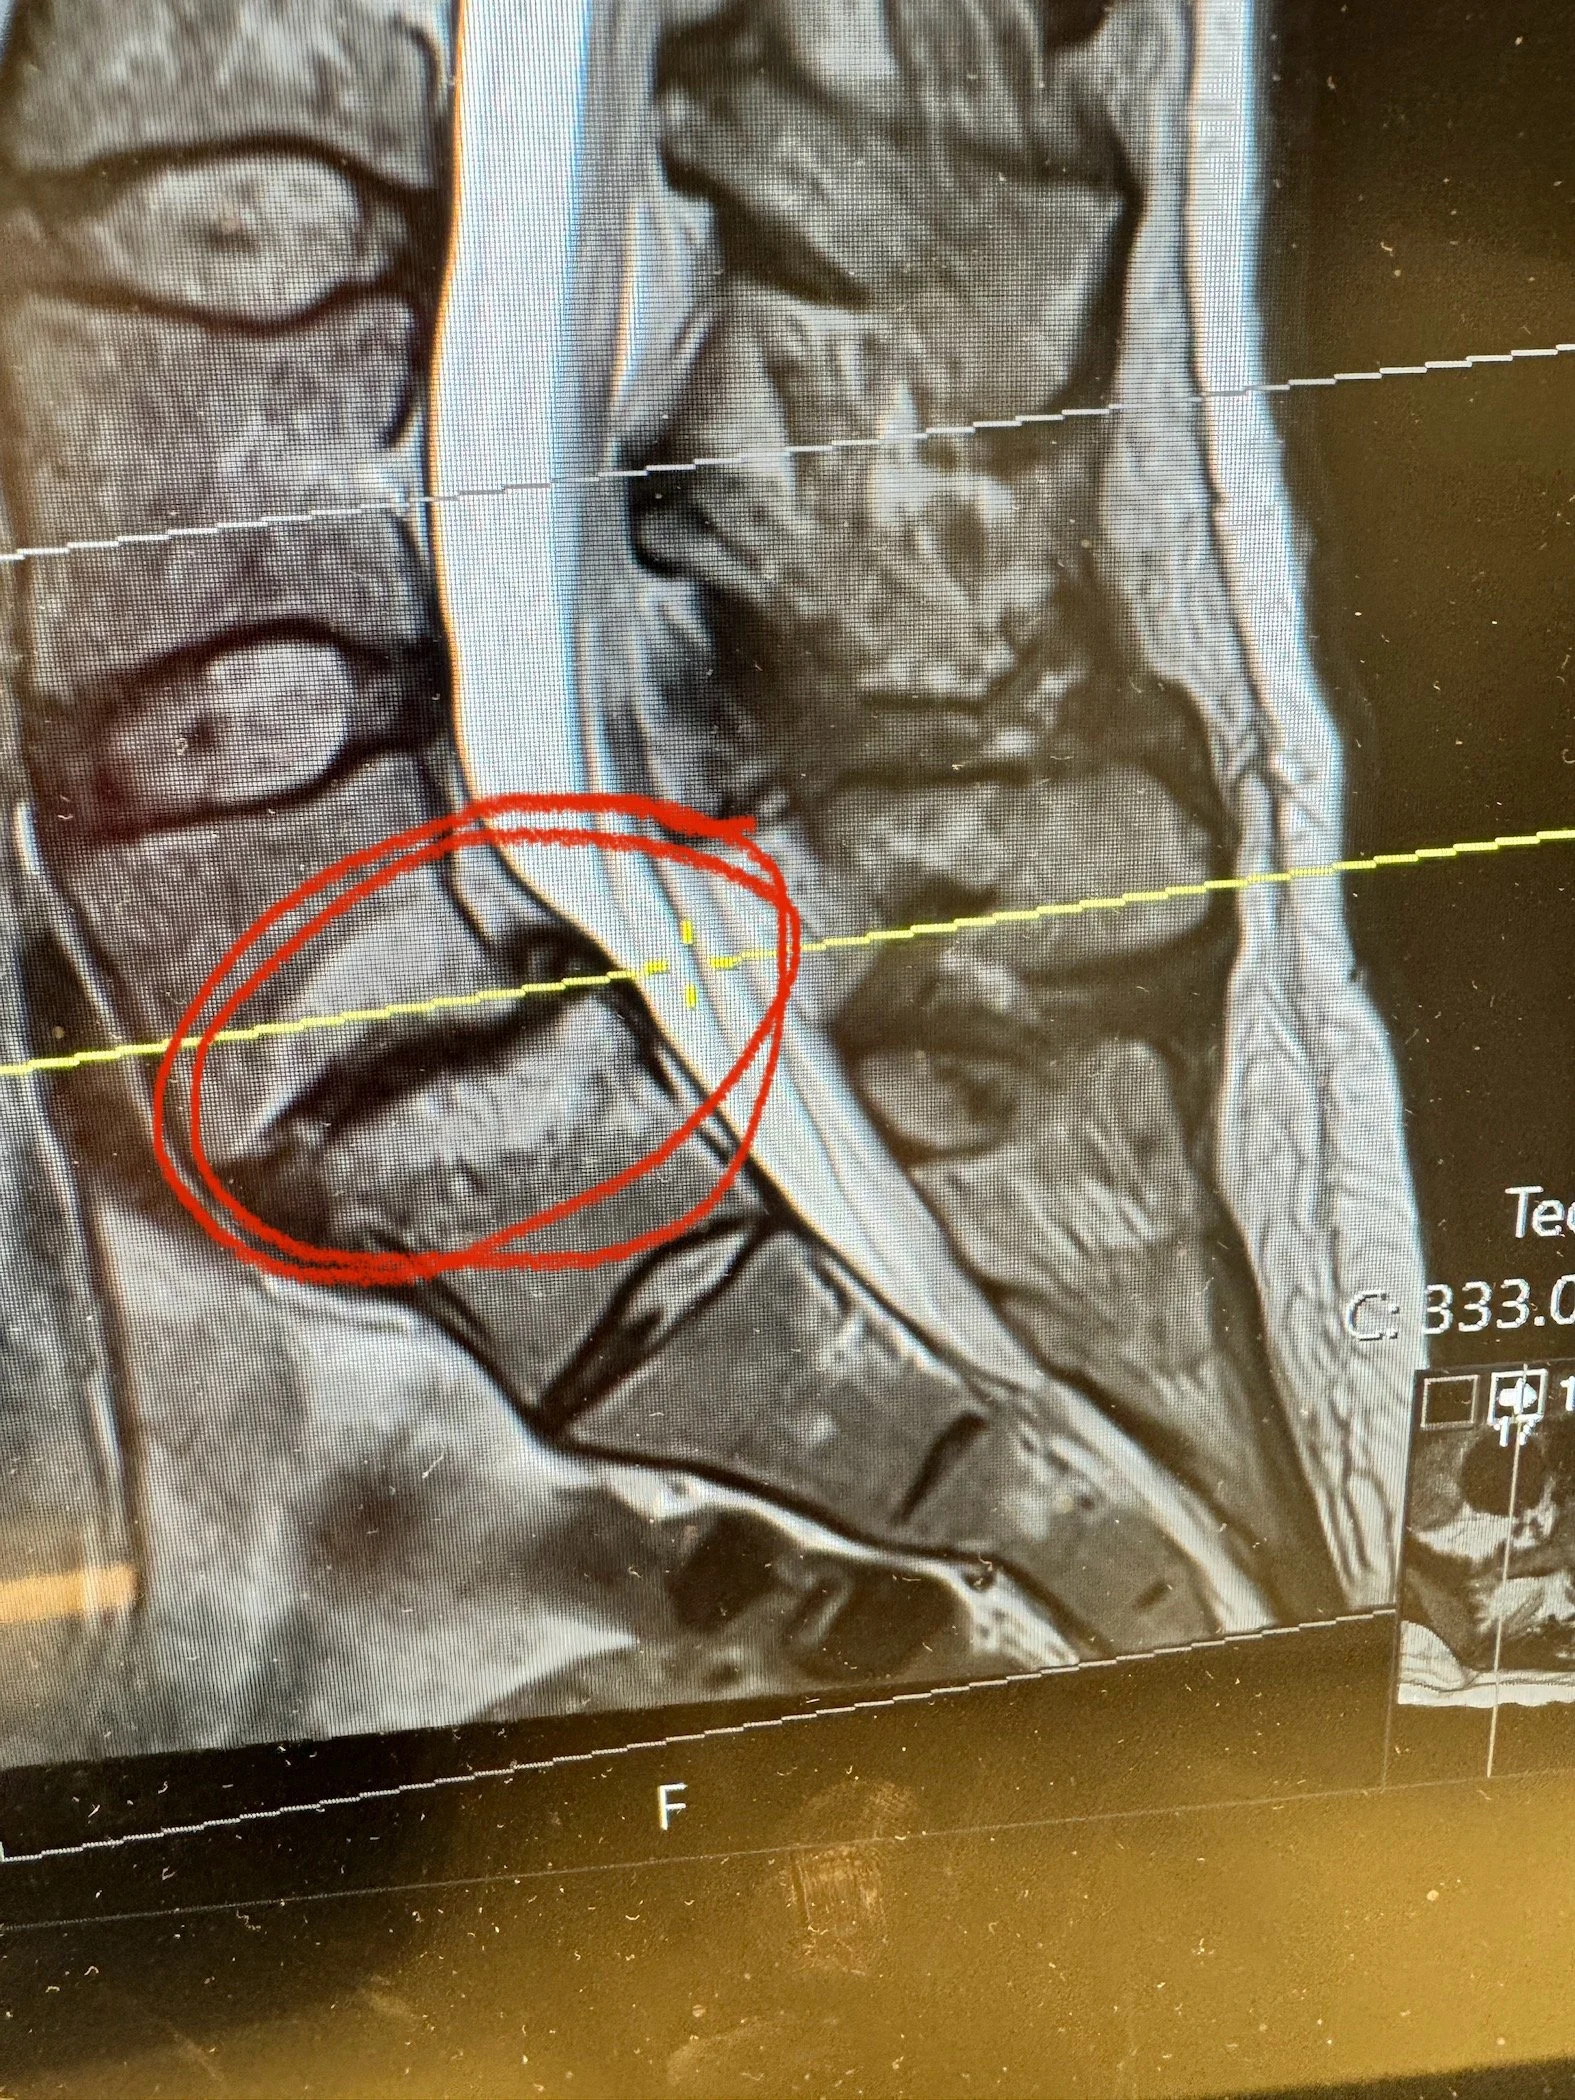

in February, I got x-rays and MRI imaging which unveiled a not so picture.

All in the L4-L5…

Unstable Grade 2 spondylolithesis

Severe disc degeneration

Bilateral pars defect (fractures of the facet joints)

Spondylolysis is movement and misalignment of vertebrae. My L4 and L5 are naturally off by 9mm just standing. When I lean forward it shifts to nearly 15mm off and when I bend backwards it’s 3mm off. This movement without a disc creates bone on bone rubbing.